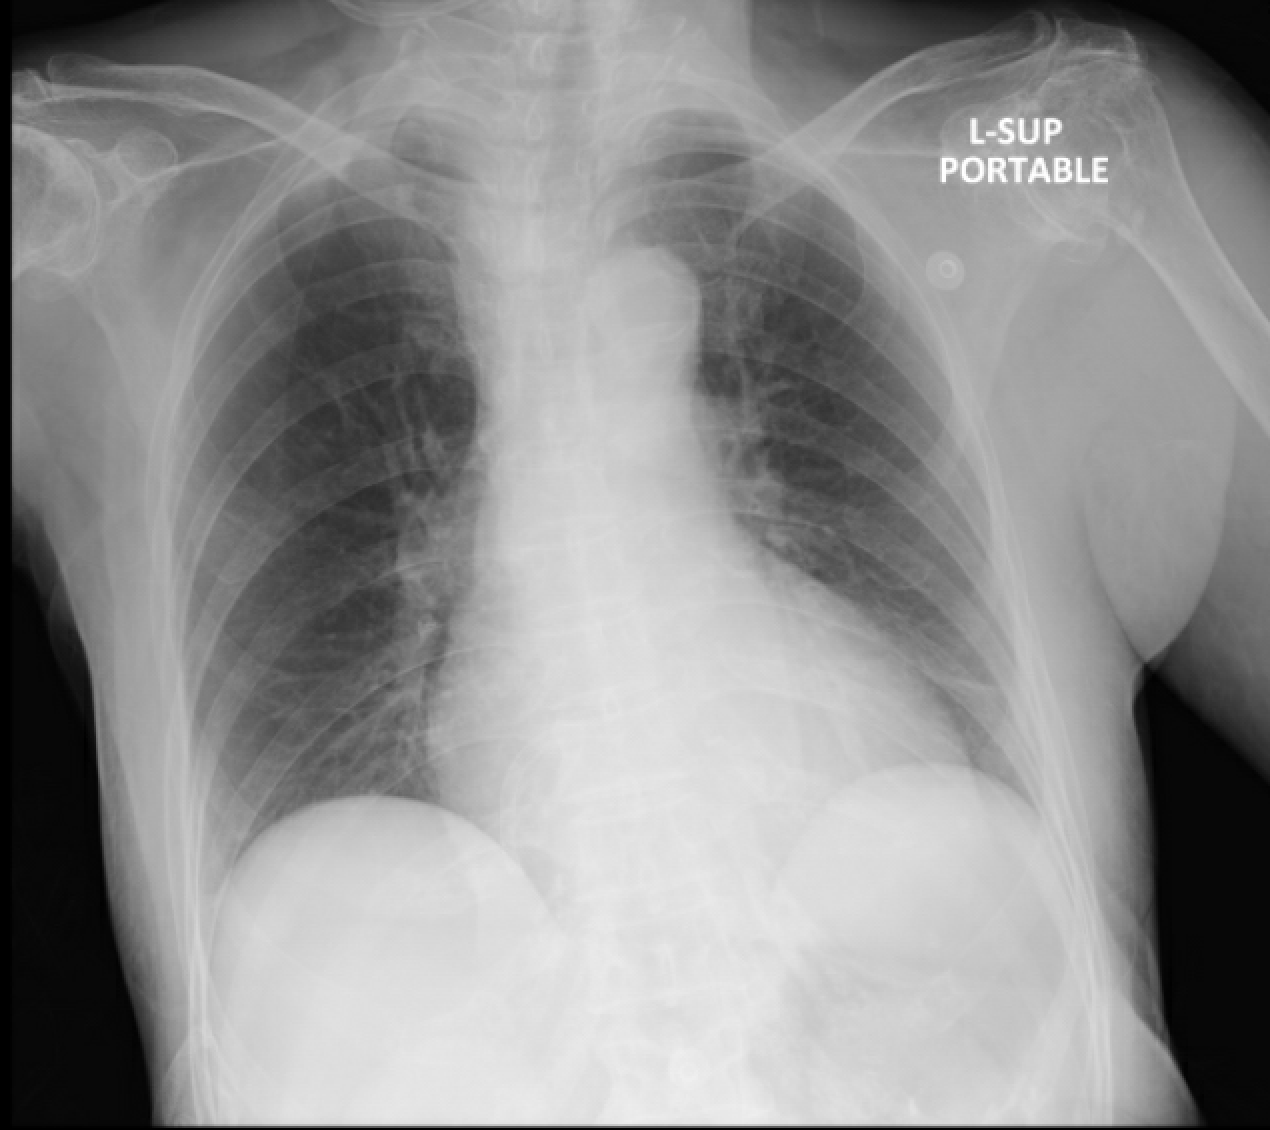

In the emergency department, an ECG revealed sinus rhythm with inferior ST elevations. A bedside echocardiogram indicated an impaired LVEF of 40%, with inferior hypokinesia. There was no pericardial effusion or signs of aortic dissection, and hemodynamics were stable. CXR showed clear lung fields. We proceeded with primary PCI.